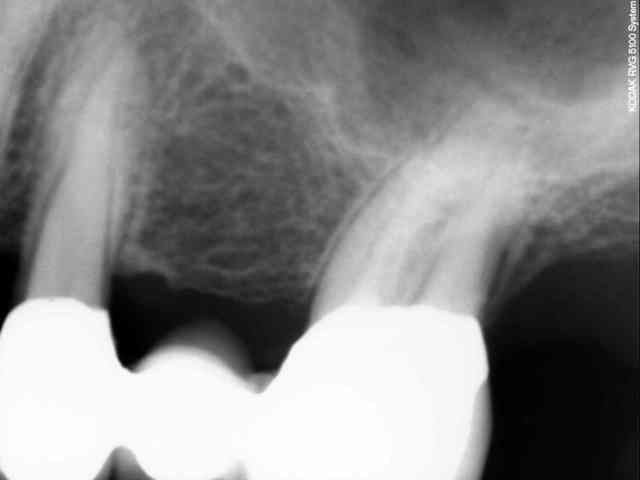

Déjà, les couronnes me paraissent bien débordantes

Deuxièmement, je ne vois pas de traitement canalaire sur ces dents. Peut etre souffrent elles de pulpite chronique

Et ne te gêne pas pour éliminer le surplomb méchamment débordant de l'obturation coronaire en distal de 47

demain je chasse, mais lundi, je vais prendre le temps de modeliser le scan, pour controler les apex

Tu as l'air de vouloir fermer les yeux sur l'origine de la douleur en devitalisant "par principe de sécurité" les 2 dents et à coté de cela tu modélises les apex... Par cet examen tu cherches à objectiver quoi exactement?

je recois un scan , je regarde tout simplement si pbs au niveau des apex!Il n'y a rien de particulier